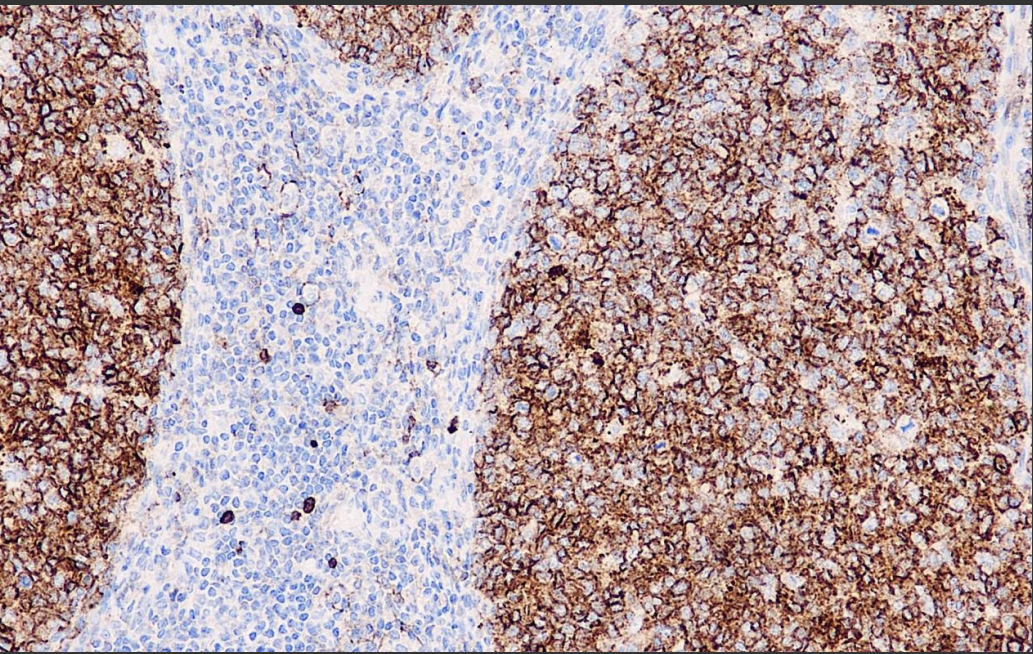

Positive control: tonsils/kidney

CD10 is a marker for follicular center cells. patients with CD10+ ALL have a better prognosis than other types, and can be positive for Burkitt's lymphoma and germinal center mother cell/germinal center follicular lymphoma. Recently, it has also been found that the mesenchyme of endometrium and adenomyoma express CD10.

CD10 Antibody Reagent binds specifically to CD10 molecular antigen. Immunohistochemistry kits containing CD10 Antibody Reagent are indicated for the precise diagnosis of endometrial mesenchymal tumors and smooth muscle tumors.